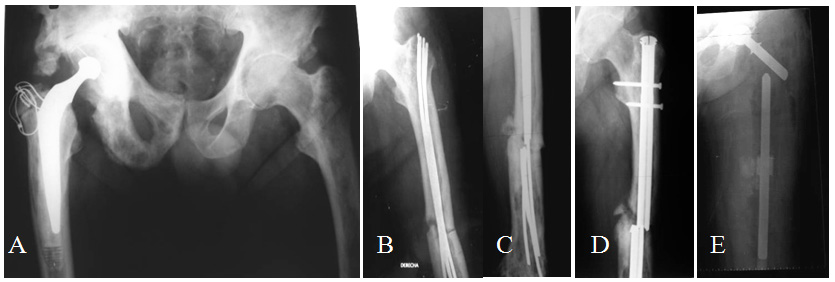

Prosthesis characteristics

In all patients, the Argentine custom made Fabroni megaprosthesis were used, which is manufactured by ROFA S.A.4-6 (Pje. Bella vista 1136 -C1416EIS- CABA, Argentina), with an approximate cost of 5.000 Euros. The prosthesis is composed by three parts. Its proximal segment is formed by two independent metallic components, the proximal stem and the femoral neck, both included in a high density polyethylene body.2,7,8 The distal femoral segment is also made of a high density polyethylene body with a cilindrical canal where the proximal stem is cemented, allowing for length regulation, and a distal constrained knee system.5,6 The third part is the rotational tibial component with a metallic distal stem (Figures 3-5).

Figure 3 The three parts of the total femur prosthesis.

Figure 4 A- dissassembled total femoral megaprosthesis. B- Total femoral megaprosthesis assembled and in place.

Figure 5 A, B y C- 94 year old lady with extremely osteopenic bone and a fracture in the short femoral shaft segment between a long stem hip prosthesis and a knee prosthesis. D- Post-operative X-ray, knee portion. E- Post-operative X-ray, hip portion.

The high density polyethylene body has essential characteristics for the appropriate functioning of the prosthesis, such as absorbing physiological loads in order to avoid fatigue failures, filling dead space after the resection, preventing the formation of hematomas and providing anchorage for tendons and muscles by means of several holes in its surface.4-6 The metallic part of the implant is made of medical grade stainless steel AISI F 138.4-6